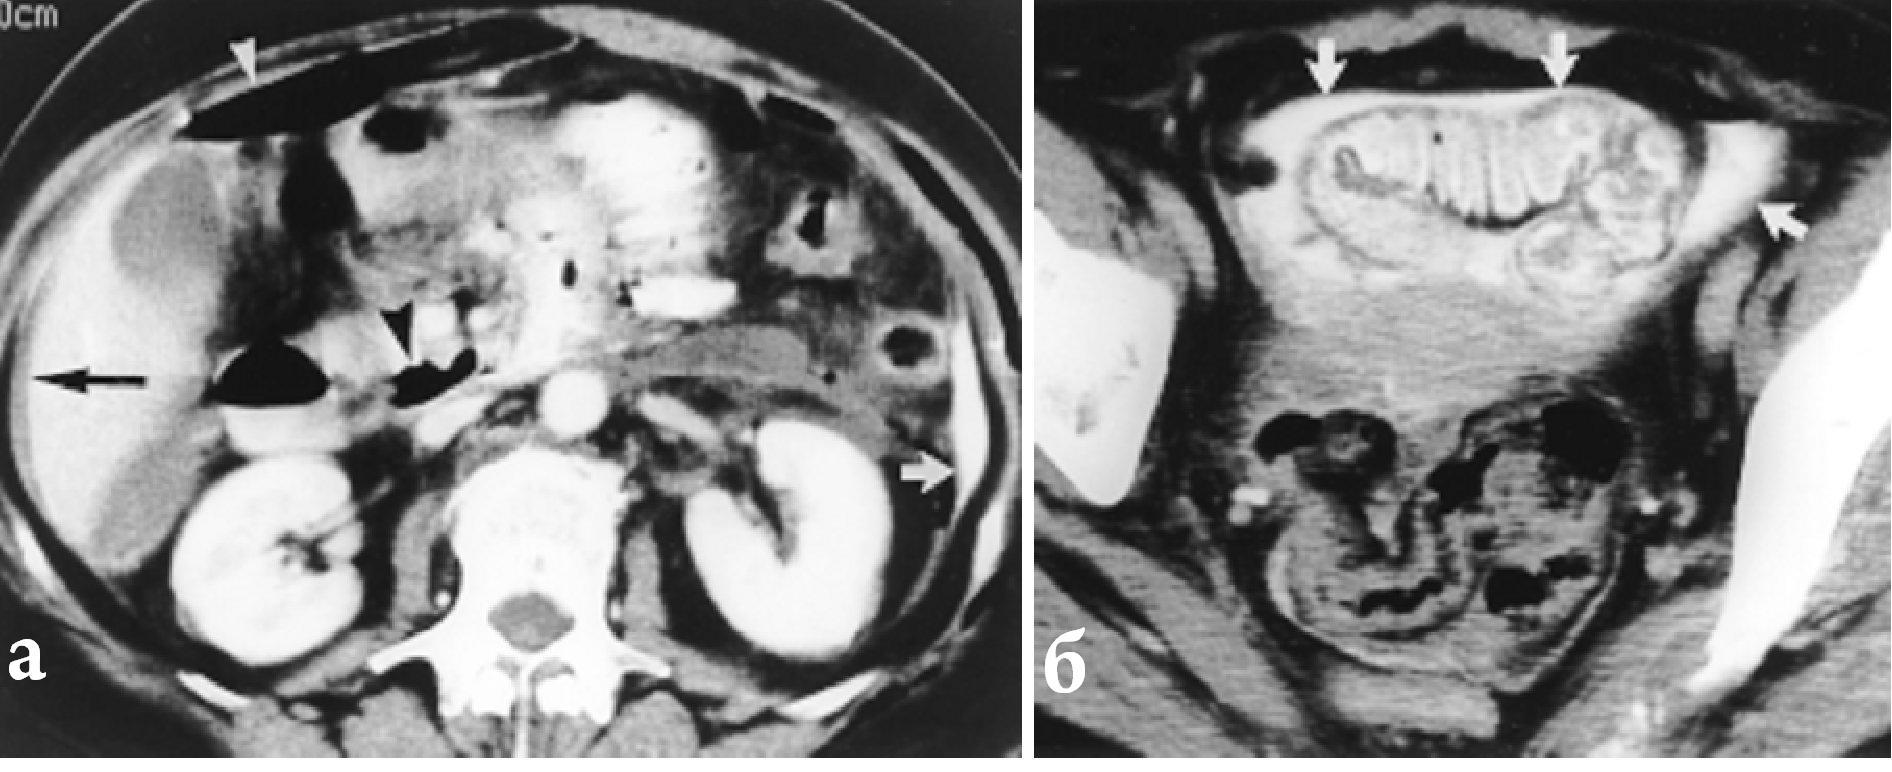

В последнее время одним из направлений, улучшающих диагностику повреждений внутренних органов брюшной полости и забрюшинного пространства является внедрение в практику компьютерной томографии (КТ), которая при травме живота занимает значительное место в диагностике гематом паренхиматозных органов, забрюшинного пространства, инородных тел.

КТ билома

Тупая травма живота. Повреждение печени.

А - МРХПГ: билома печени (стрелка); Б - КТ: дренаж в просвете биломы (стрелка).